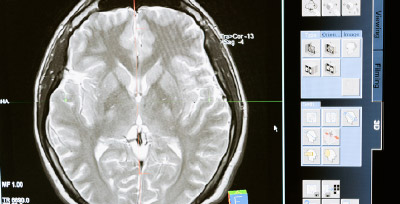

Crean método que detecta el alzheimer con 99 % de precisión

Un grupo de investigadores de Kuanas ha desarrollado un método de aprendizaje profundo a partir de imágenes cerebrales para predecir el alzheimer con una precisión de más del 99 %. Este método consiste en delegar el procesamiento de imágenes a la inteligencia artificial para obtener un análisis más rápido y preciso. Después el profesional de la salud analiza con mayor profundidad y da un diagnóstico y tratamiento temprano y oportuno para el paciente.